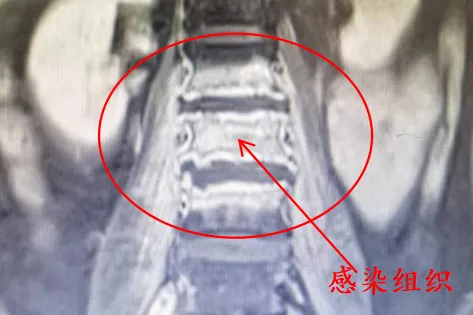

黎华文仔细了解了苏阿姨的情况后高度重视,立刻安排了全面的检查,发现苏阿姨盆腔的肿物半年已经长大到约 104*99*113 mm,并且有代谢增高,与周围组织、血管关系紧密,有恶性肿瘤的可能。

但同时,黎华文也告诉苏阿姨,这种骶前肿瘤,在过去被视为「手术禁区」,主要来源于腹膜后间隙的脂肪、疏松结缔组织、筋膜、肌肉、血管、神经、淋巴组织以及胚胎残留组织,发病率占全身各类肿瘤不足 0.5%。该类肿瘤位置较深、发病隐匿,常常在肿瘤巨大、侵犯或挤压周围脏器发生合并症时才被发现。

手术切除是该肿瘤的主要治疗手段。但同时因为肿瘤位于骶骨前腹膜后,位置深、骶前静脉丰富,剥离肿瘤过程中极容易出现无法控制的静脉窦出血,术中出血风险极大,手术难度极高,做这样一台手术就是打一场硬仗!

专家讨论认为,腹膜后肿瘤直径超过 10 cm,并且位于骶前,与骶前静脉丛关系密切,肿瘤右侧压迫右侧髂内动静脉,手术难度大、风险高。但肿瘤边界尚清楚,未见明显的骨质侵犯,手术关键是解剖清楚、控制好出血。